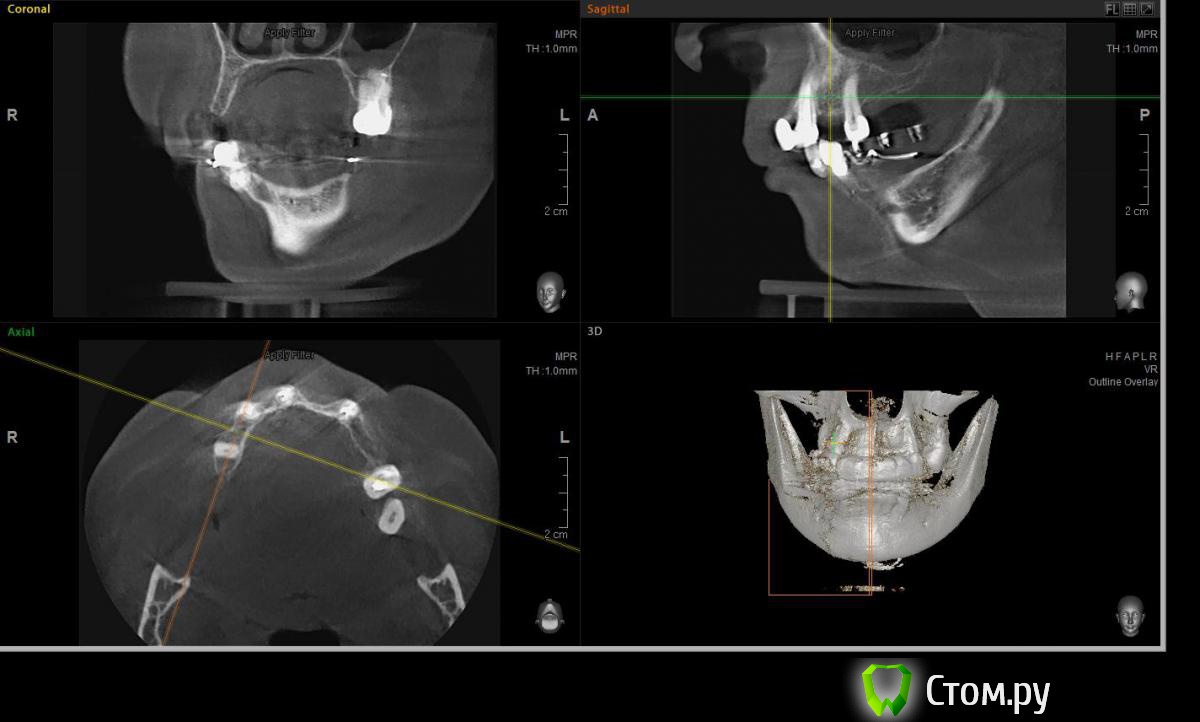

Евгений Ходыкин Опубликовано 22 июля, 2014 Автор Поделиться Опубликовано 22 июля, 2014 Дабы не плодить тем решил очередной случай выложить сюда Решили с пациенткой пока начать с в.ч. В планах имплантация в область отсутствующих 1.6, 1.4, 1.2, 2.1, 2.2, 2.4, 2.5. С 1.6 самому более менее все понятно, мануальных навыков хватит) Прошу помощи коллег относительно остальных областей. Фронт особливо печален... Забегая наперед скажу, что блоки еще не делал. Ауто точно пока брать не планирую, ибо нет даже теоретических навыков. Хочу начать все-таки с аллоблоков. У кого какие будут мнения, заранее спасибо) Ссылка на комментарий